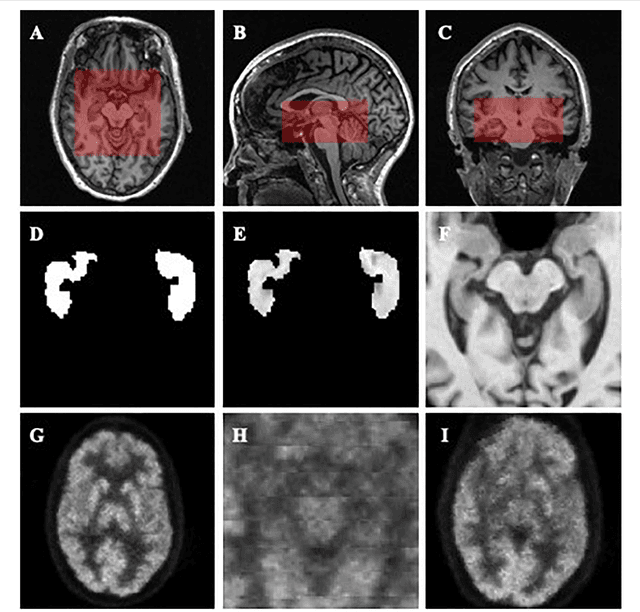

Abstract:Alzheimer's Disease (AD) is one of the most concerned neurodegenerative diseases. In the last decade, studies on AD diagnosis attached great significance to artificial intelligence (AI)-based diagnostic algorithms. Among the diverse modality imaging data, T1-weighted MRI and 18F-FDGPET are widely researched for this task. In this paper, we propose a novel convolutional neural network (CNN) to fuse the multi-modality information including T1-MRI and FDG-PDT images around the hippocampal area for the diagnosis of AD. Different from the traditional machine learning algorithms, this method does not require manually extracted features, and utilizes the stateof-art 3D image-processing CNNs to learn features for the diagnosis and prognosis of AD. To validate the performance of the proposed network, we trained the classifier with paired T1-MRI and FDG-PET images using the ADNI datasets, including 731 Normal (NL) subjects, 647 AD subjects, 441 stable MCI (sMCI) subjects and 326 progressive MCI (pMCI) subjects. We obtained the maximal accuracies of 90.10% for NL/AD task, 87.46% for NL/pMCI task, and 76.90% for sMCI/pMCI task. The proposed framework yields comparative results against state-of-the-art approaches. Moreover, the experimental results have demonstrated that (1) segmentation is not a prerequisite by using CNN, (2) the hippocampal area provides enough information to give a reference to AD diagnosis. Keywords: Alzheimer's Disease, Multi-modality, Image Classification, CNN, Deep Learning, Hippocampal